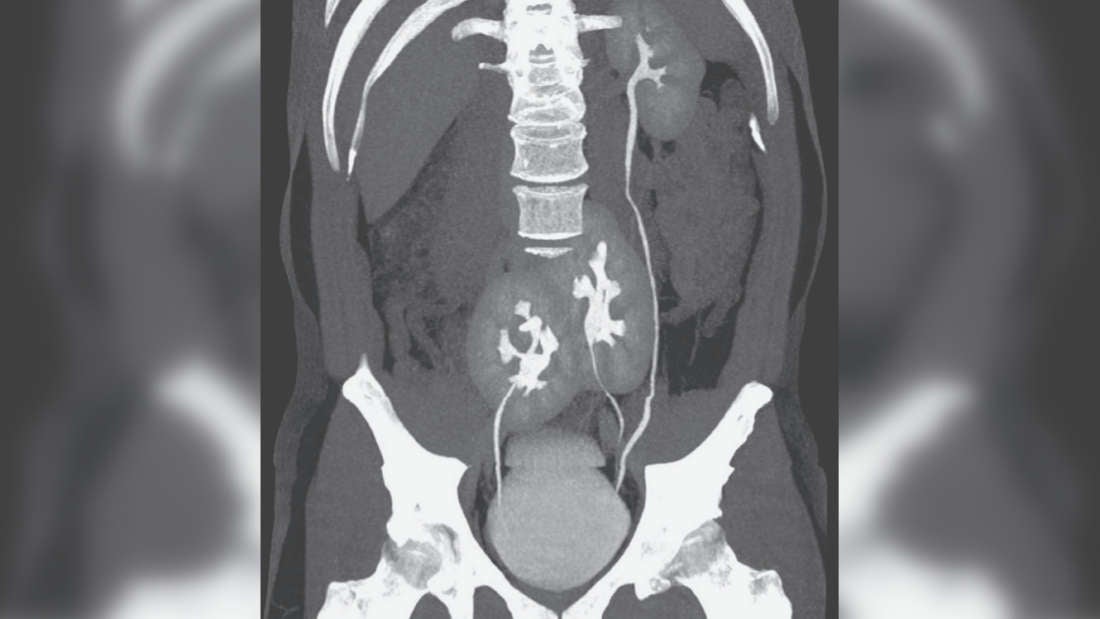

El caso apareció publicado en New England Journal of Medicine (NEJM) la semana pasada. Un hombre de 38 años visitó un hospital en la ciudad de São Paulo debido a un fuerte dolor lumbar. La posterior tomografía computarizada (TC) reveló que el paciente tenía tres riñones en su abdomen: un riñón izquierdo de apariencia normal, y dos riñones fusionados.

Cuentan en su informe los expertos que los riñones del paciente son una anormalidad congénita poco común que probablemente ocurrió durante el desarrollo embrionario, cuando una sola estructura primitiva similar a un riñón se divide en dos.

Si bien es extremadamente raro, dicha condición se ha documentado un par de veces antes. Conocido como riñón supernumerario, se cree que hay menos de 100 casos de la afección en la literatura médica, incluidos varios de hace más de un siglo.